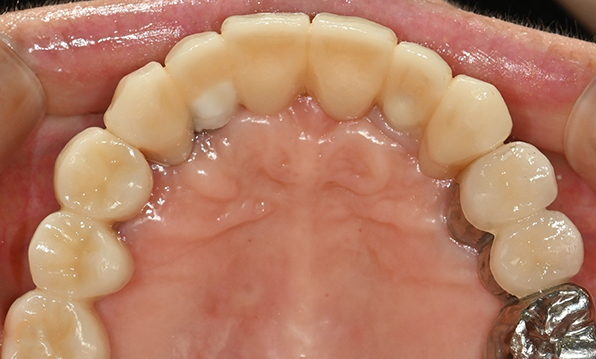

잇몸뼈가 얇은 상태

-

잇몸뼈 충분히 이식 후 임플란트 식립

성공을 위한 노하우, 잇몸뼈 재건 기술

전체 임플란트를 해야하는 환자들은

대부분 고령의 환자들로 오랜 틀니 사용

또는 노화로 인해 치조골이

거의 남아있지 않는 경우가 많습니다.

이 때, 치조골 이식을 병행하여 잇몸뼈 재건 후 안정적인 임플란트 식립을 하고 있습니다.